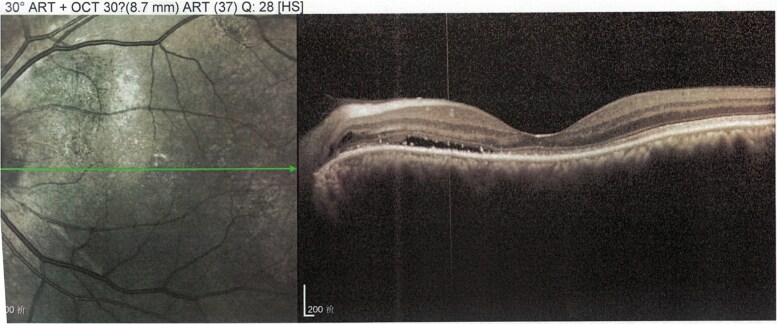

Figure 2.

Optical coherence tomography (OCT) scan of the left eye of case 2. At the diagnosis of Graves orbitopathy, before triamcinolone acetonide injections. OCT images at presentation demonstrating a small amount of fluid accumulation beneath the neurosensory retina, with a subretinal fluid height of 186 μm.

A 60-year-old male patient with a history of hyperthyroidism and Graves orbitopathy (GO) presented with vision loss in the LE over the past 2 weeks. The patient was diagnosed with GO 1 year prior. At that time, OCT revealed a small accumulation of fluid beneath the neurosensory retina, leading to serous detachment (Fig. 2). He was admitted to the 900 Hospital of the Joint Service Support Force of the People's Liberation Army of China for intravenous glucocorticoid (GC) therapy, with a cumulative dose of 4.5 g of methylprednisolone, administered in 10 weekly infusions (3 consecutive days of infusions of 0.5 g during the first week, 3 weekly infusions of 0.5 g, followed by 6 weekly infusions of 0.25 g). Thyroid dysfunction was managed with 10 mg thiamazole given orally twice a day. The patient experienced blurred vision after intravenous GC therapy, which resolved after 6 months. Three months prior, the patient received 5 peribulbar injections of triamcinolone acetonide (TA) 40 mg every 2 weeks, leading to acute vision loss and metamorphopsia in the LE. The patient was referred to the endocrinology department for optimal treatment of GO.

Figure 4.

Optical coherence tomography (OCT) scan of the left eye of case 2. After triamcinolone acetonide injections. OCT images showing serous detachment of the neurosensory retina accompanied by a small retinal pigment epithelium detachment, consistent with the diagnosis of central serous chorioretinopathy, with a subretinal fluid height of 583 μm.

Visual acuities were 0.25 in the LE and 0.6 in the RE, with best-corrected visual acuity (BCVA) values of 0.3 in the LE and 1.0 in the RE. The intraocular pressure was 16.9 mm Hg in the LE and 18.0 in the RE. Physical examination revealed exophthalmos in both eyes, eyelid edema, conjunctival congestion, and diplopia in the right, upper-right, lower-right, and left gaze. OCT showed serous detachment of the neurosensory retina, accompanied by a small RPE detachment (Fig. 4). Thyroid function tests revealed a free triiodothyronine (FT3) level of 4.10 pg/mL (6.23 pmol/L; normal reference range, 1.82-4.14 pg/mL; 2.76-6.3 pmol/L), free thyroxine (FT4) of 11.98 pg/mL (15.57 pmol/L; normal reference range, 8.02-18.71 pg/mL; 10.42-24.32 pmol/L), and thyrotropin (TSH) of 0.01 µIU/mL (0.01 mIU/L; normal reference range, 0.35-5.5 µIU/mL; 0.35-5.5 mIU/L), with thyrotropin receptor antibody (TRAb) level of 13.05 U/L (normal reference range, ≤ 1.75 U/L). Orbital magnetic resonance imaging showed severe inflammation and hypertrophy in the superior, inferior, and internal rectus muscles, and thyroid ultrasonography suggested diffuse goiter and thyroid inflammation.